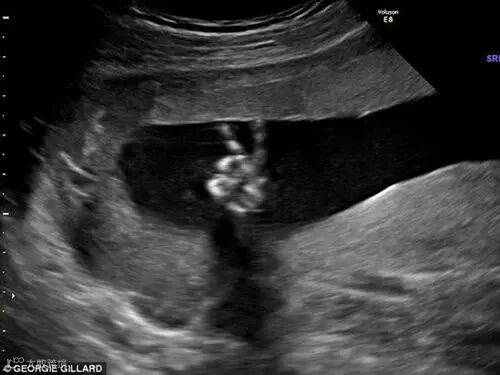

“剪刀手”无处不在 腹中胎儿也会比“V字”

据英国《每日邮报》报道,英国一对准父母在胎儿的超声波图像上发现宝宝正用小手比出“剪刀手”——V字手势。准妈妈表示,胎儿的这个手势让她觉得很安心。这对夫妇决定如果是个男孩,就给他起名为温斯顿,因为剪刀手最早源于温斯顿·丘吉尔,是世界和平的象征。